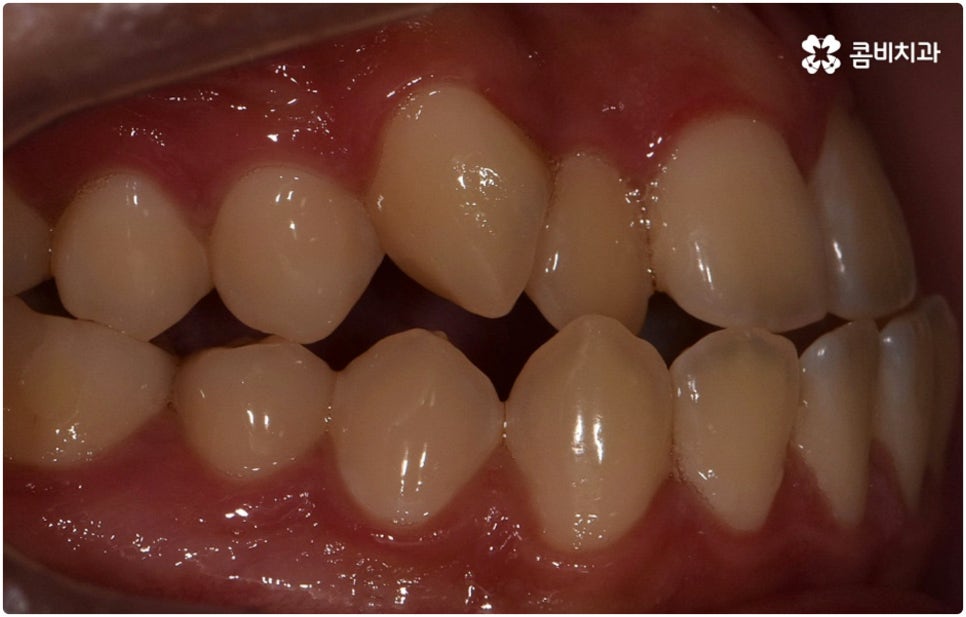

부정교합은 부정교합 1급, 부정교합 2급, 부정교합 3급 이렇게 세가지 종류로 나눌 수 있는데요. 부정교합 1급은 이를 다물었을 때 위아래 어금니는 잘 맞물리지만 덧니가 있거나 치아 사이가 살짝 벌어져 있는 경우처럼 치열이 삐뚤어진 경우를 말하는 것으로 골격이나 구조적인 부분에는 크게 문제가 없기 때문에 정도가 심하지 않다면 보다 빠르고 간편한 교정 치료가 가능한 케이스라고 할 수 있어요. 부정교합 2급은 상악이 하악보다 더 튀어나온 상태로 위에서 언급했던 무턱, 돌출입이 여기에 속하며 반대로 부정교합 3급 은 주걱턱처럼 하악이 상악보다 튀어나온 상태를 의미하고 있습니다.

부정교합 2급, 부정교합 3급 과 같이 구조적인 부분에 원인이 있는 문제라면 잇몸뼈가 다 굳고 난 다음인 중장년 성인분들의 경우 교정 치료를 받는 것이 과연 부정교합 개선에 효과가 있을까 궁금해 하실 수 있어요. 특히 턱관절 이상 문제는 수술을 통해서만 고칠 수 있다고 알고 계셨던 분들은 부담을 느끼고 치료를 미루셨을 수 있는데요. 물론 성인분들의 경우 상황에 따라, 예를 들어 정도가 매우 심한 부정교합 3급 케이스라면 악교정수술을 받아야 할 수도 있습니다. 또한 대부분의 부정교합 2급, 부정교합 3급 케이스들 같은 경우 초등학교 고학년에서 중학교 저학년 사이에 교정 치료를 시작하는 것이 좋다고 권유하는 것도 사실인데요, 그 이유는 아무래도 치아 이동 속도가 빠르고 전반적인 발달 상황에 맞추어 자연스럽게 치료를 진행할 수 있는 성장기의 특성상 이 시기부터 지속적으로 턱뼈 크기 부조화를 조절하고 상하악의 올바른 성장을 유도하는 게 보다 효율적이기 때문이라고 할 수 있어요.